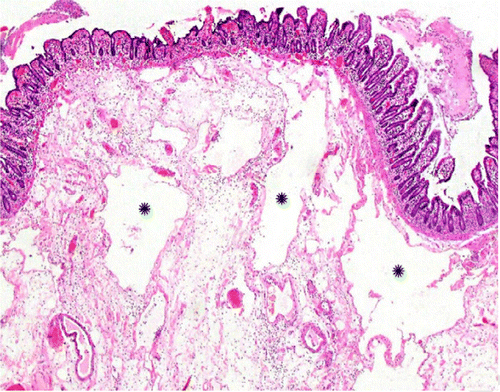

В частности, как пояснил специалист, у некоторых пациентов с COVID-19 внезапно развивался пневматоз - патологическое состояние системы пищеварения, при котором газы проникают в толщу стенки кишечника и образуют там воздушные кисты. Кроме того, у нескольких людей было выявлено необычное желтое обесцвечивание кишечника, еще у трех больных - инфаркт кишечника.

© Radiology